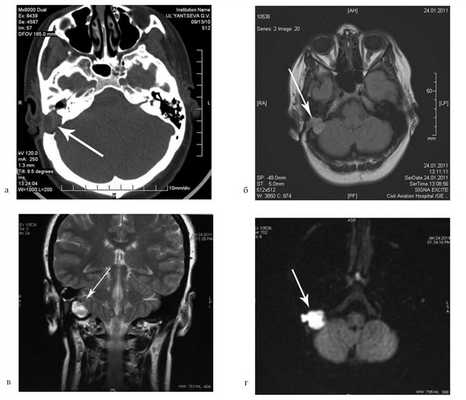

На КТ височных костей справа послеоперационная полость, заполненная мягкотканным образованием, определяется большой костный дефект в направлении сигмовидного синуса и мозжечка (рис. 2, а). Рисунок 2. КТ и МРТ височных костей больной У. с хроническим правосторонним средним отитом. Состояние после радикальной операции (1993 г.), санирующей операции с мастоидопластикой и тимпанопластикой (2003 г.). Холестеатома. Парез лицевого нерва. а — КТ; б — МРТ основания черепа в режиме Т1; в — в режиме Т2; г — в режиме non-EPI DWI.

Больной была выполнена МРТ (рис. 2, б—г).

В режимах Т2 и non-EPI DWI определяется сигнал высокой интенсивности, в режиме Т1 — низкоинтенсивный сигнал. Это может свидетельствовать о наличии холестеатомы мастоидальной полости и пирамиды височной кости. Диагноз: хронический правосторонний средний отит; состояние после радикальной операции в 1993 г. и санирующей операции с мастоидопластикой и тимпанопластикой в 2003 г.; холестеатома; парез лицевого нерва.

На КТ правой височной кости определяется затемнение в области аттика и антрума, цепь слуховых косточек сохранена (рис. 3, а). Рисунок 3. КТ и МРТ височных костей больного А. с адгезивным средним отитом справа, фиброзной облитерацией аттика. а — КТ; б — МРТ основания черепа в режиме Т1; в — в режиме Т2; г — в режиме non-EPI DWI.

Пациенту выполнена МРТ основания черепа по описанной методике (рис. 3, б—г).

В режиме Т1 и Т2 справа определяется очаг с высокой интенсивностью сигнала, тогда как в режиме non-EPI DWI патологических образований не выявлено. Диагноз: адгезивный средний отит справа, фиброзная облитерация аттика.